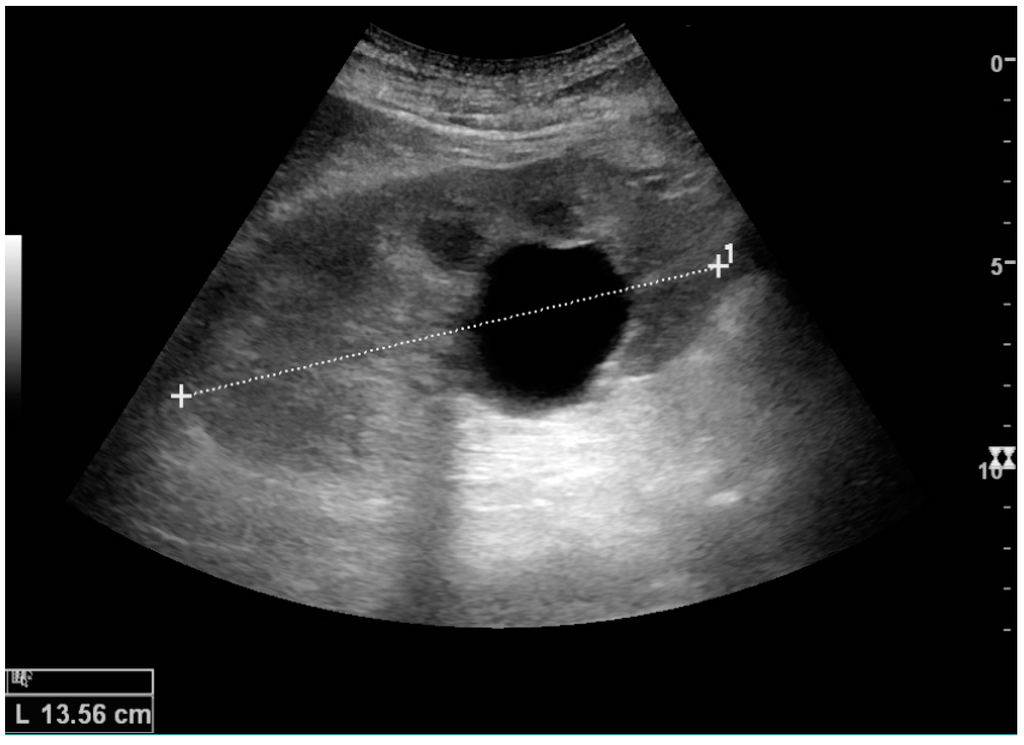

The hydronephrosis is typically graded visually and can be divided into five categories going from a slight expansion of the renal pelvis to end-stage hydronephrosis with cortical thinning (Figure 15) [16]. The evaluation of hydronephrosis can also include measures of calyces at the level of the neck in the longitudinal scan plane, of the dilated renal pelvis in the transverse scan plane and the cortical thickness, as explained previously (Figure 16 and Figure 17) [4].

Figure 16. Hydronephrosis with dilated anechoic pelvis and calyces, along with cortical atrophy. The width of a calyx is measured on the US image in the longitudinal scan plane, and illustrated by ‘+’ and a dashed line.